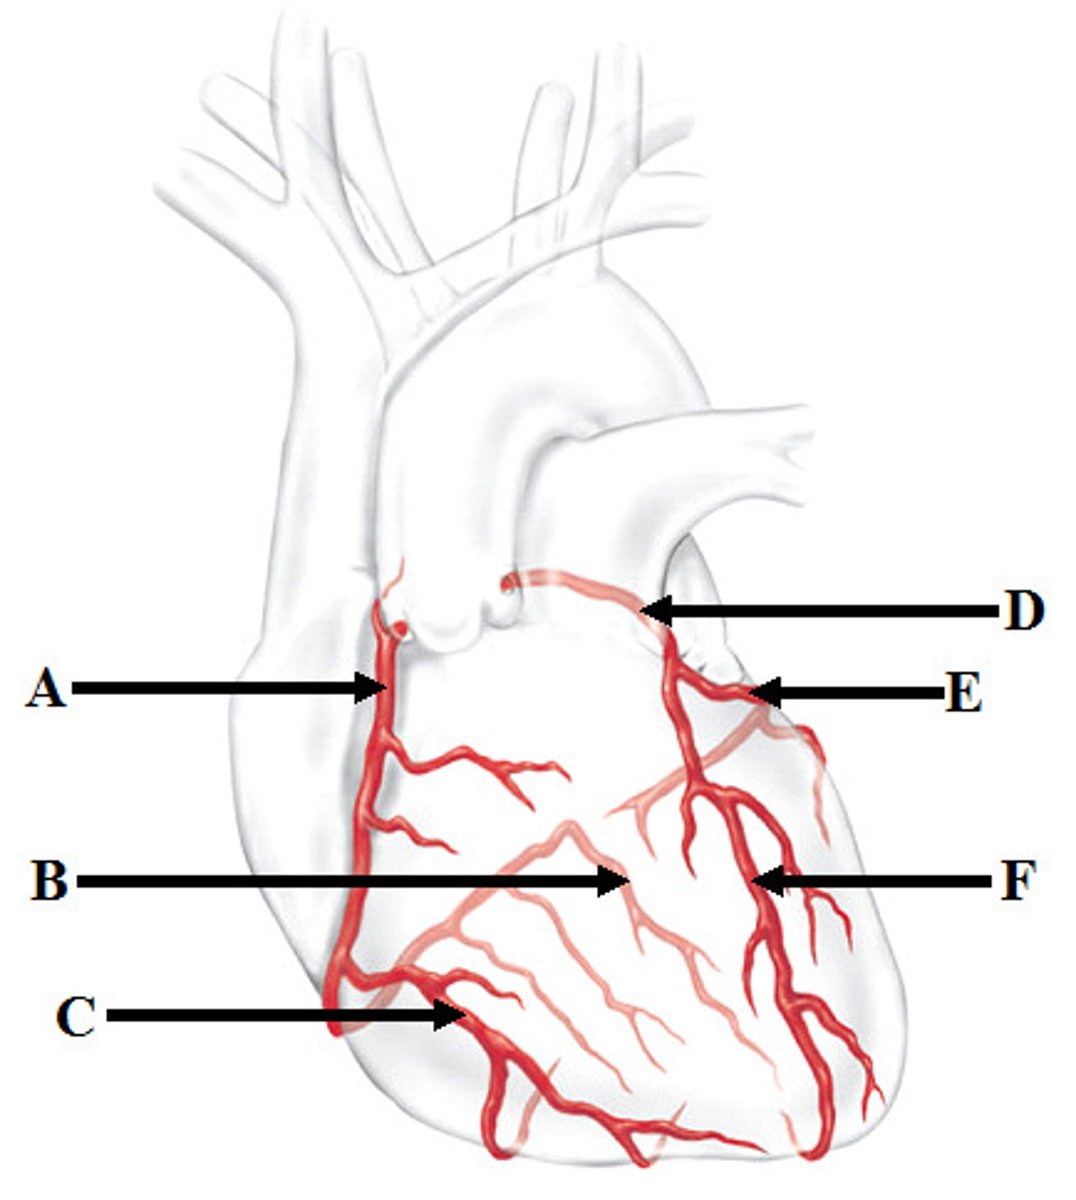

Coronary arteries (right (A) and left(D))

Marginal artery (C) and Posterior Interventricular artery (B)

Branches of right coronary artery

Anterior Interventricular artery (F) and Circumflex artery (E)

Branches of the left coronary artery